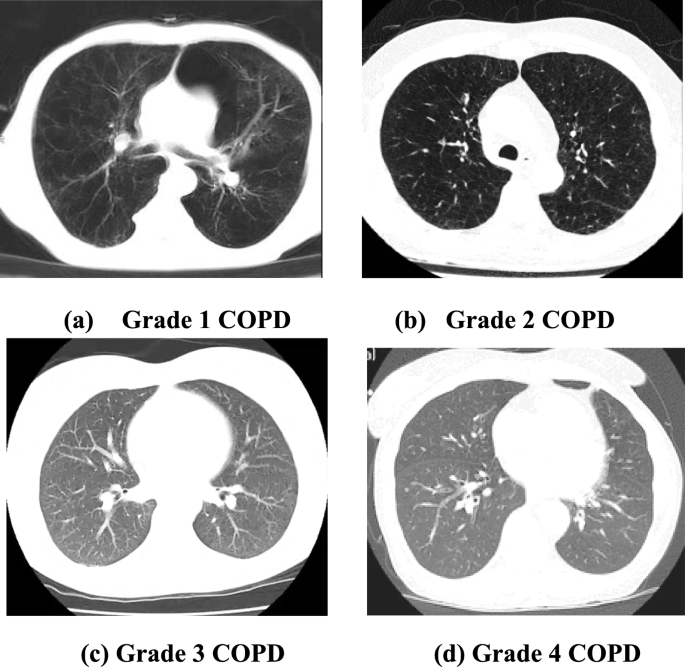

Hence there arises a huge need for an automated system that identifies and classifies the various stages of COPD depending upon the severity. Also, the economic burden that the disease places on its patients is exceedingly high and is estimated to be around 6% of the European Union’s financial budget annually. It is a heterogeneous disease that involves numerous smaller respiratory disorders. It is usually caused by the continuous exposure of the air tract and the lungs to micro particles that is often toxic and allergic4. It has four distinct stages classified by the Global initiative for chronic Obstructive Lung Disease (GOLD) such as stage 1, stage 2, stage 3, and stage 4. While the first stage is considered to be mild and the second one moderate, stages 3 and 4 are considered to be severe and very severe in nature. As the disease progresses, symptoms such as breathlessness, cough, dyspnea, and exacerbations intensify5. Although many imaging modalities such as magnetic resonance imaging, ultrasound and computed tomography images are available, specialists believe that the CT images of the affected lungs will function as the proper base for the identification of COPD. Various other signals such as electromyography signals, sounds of breathing etc. can also be used for identifying the disease. By identifying the disease in earlier stages, we can prevent the disease from progressing to further stages and also reduce the costs associated to the treatment.

The proposed system is implemented within the environment of python including pre-defined libraries of TensorFlow and Keras. 560 self-acquired CT lung images were divided in the ratio 80:20 for KELM classifier training. 448 images are used for training the classifier and 112 images for evaluating it. For grade 1 COPD, 104 images were used to train the classifier, and 30 images were used for testing. For grade 2 COPD, 113 images were utilized for training and 25 for testing. Similarly for grade 3 and 4, 131 and 157 images were employed in total. The details of dataset division are given in Table 1 below.

Figure 5 shows the sample CT images of patient’s lungs affected by COPD.